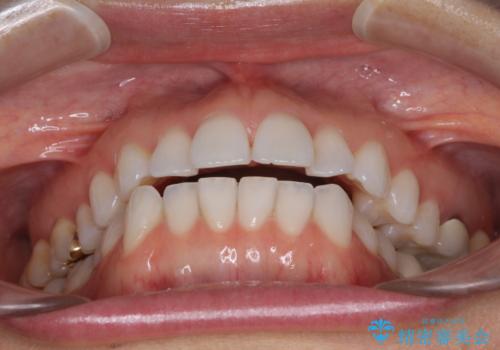

ちょっとしたデコボコをしっかりと改善したい インビザライン矯正

- 前歯のデコボコと上下スペースと前歯の隙間を気にして来院された患者様です。

目立たない装置を希望とのことでインビザラインにより、デコボコを解消しつつ、上下の前歯の隙間を閉じていくこととしました。

デコボコはあっという間に解消されましたが、上下前歯の隙間がなかなか解消されませんでした。

飲み込みの際に舌を前方に突出する癖があり、飲み込みの度に前歯に強く接触していたため、上下前歯の隙間が維持されていました。

舌の訓練を徹底していただいたことで、徐々に隙間は解消され、きれいな歯列に整えることができました。